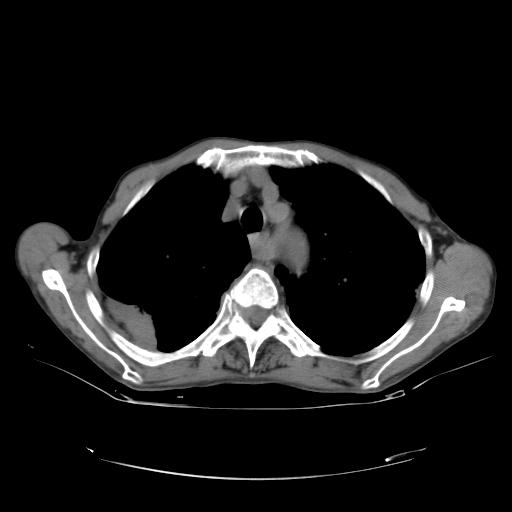

女,72岁,咳嗽一周余,突发右下肢无力二天。

来院做头颅+胸部ct平扫

遂加作增强:

胸部病变平扫35hu,增强强化至70hu

这个病人首先是胸部病变的定位到底是肺内还是肺外。仔细观察块影位于胸膜下,与胸膜间有透亮带,且近端血管未见明显推移而是引流样改变,形态分叶,说明这个病灶位于肺内胸膜下。很可能是腺癌,腺癌最易致颅内高密度转移灶。局部胸膜有侵犯。

本例颅内见多发大小不等高密度灶,有强化及水肿;另外,胸锁关节层面可能是第四胸椎及右侧肋骨起始部骨质欠连续,椎旁软组织肿胀,建议调骨窗观察。

基于以上原因,所以炎性肿块或胸膜间皮瘤不考虑。

诊断:右下肺癌伴颅内、胸椎、肋骨转移可能性最大。